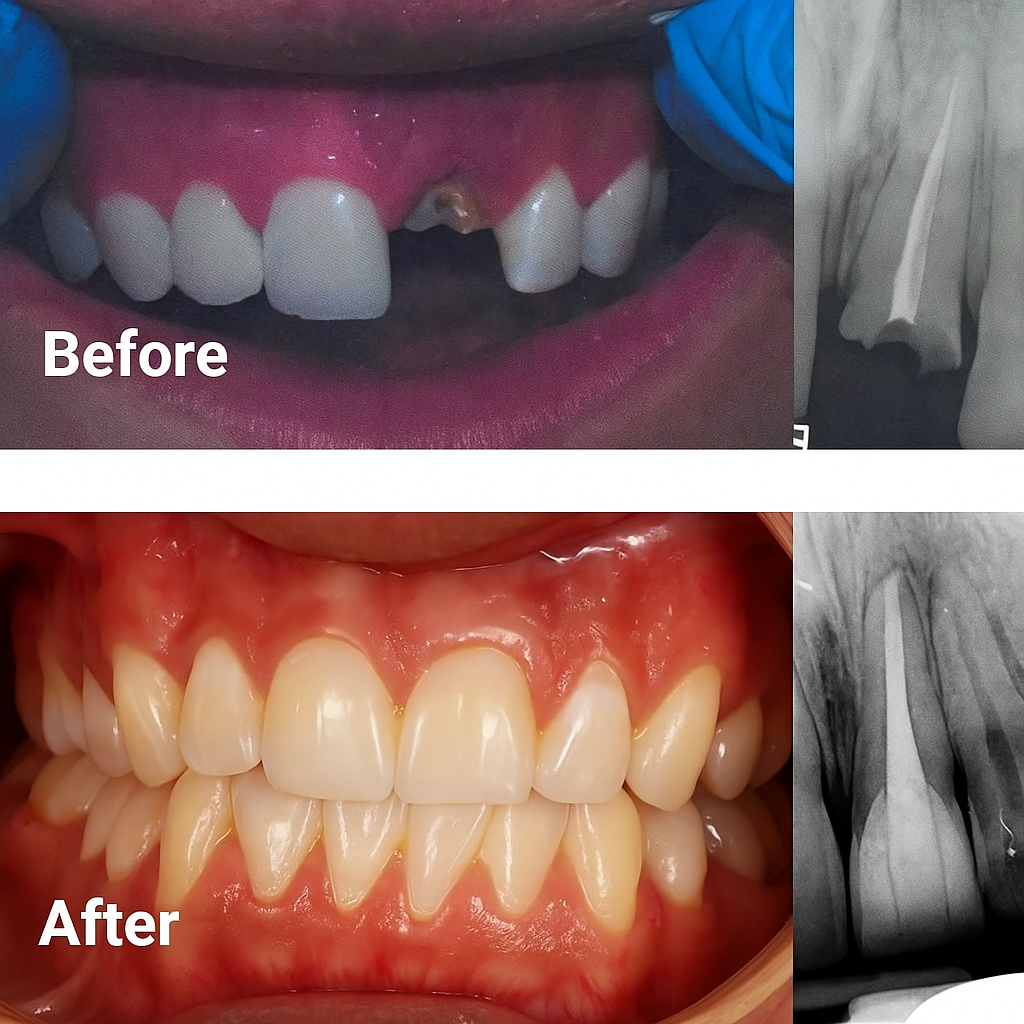

Dental Implants

They are artificial tooth roots that replace your lost natural roots. During the surgical procedure, your dentist will implant them into your jawbone and stable a new prosthetic tooth on top of it. It will fuse with your jawbone, offering a natural look and a reliable option to restore your smile. They are made of titanium.

They are the most effective option to replace missing teeth, and they provide a natural look and feel. Adjacent teeth remain intact and are permanent. The cons are that they are expensive and require surgical procedures.